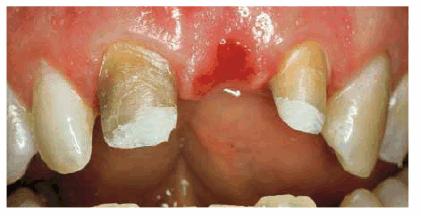

TREATMENT: Because saving teeth was a step-by-step procedure involving

endodontic treatment, periodontal surgery, and reconstructive techniques, the

treatment plan could be changed if one of the suggested treatments failed.

Endodontic therapy had already been completed on both central incisors. These

surgical procedures were performed next: removal of the tooth fragments that

were fractured vertically, labial and lingual gingivectomy and gingivoplasty,

palatal ostectomy, and labial frenectomy (Figur 323s1823d e 18-7C). Approximately 5 mm of palatal

plate was removed to expose new margins on the fractured teeth (Figur 323s1823d e 18-7D). After the tissue healed, gold

posts were constructed and cemented on the two maxillary incisors (Figur 323s1823d es 18-7E to

H). Final

preparations were made, and impressions for aluminous porcelain crowns were

made. The two crowns were seated (Figur 323s1823d es 18-7I

and J Figur 323s1823d e 18-7K is a radiograph of the teeth at the

end of treatment.

Figur 323s1823d e 18-7C and D: Following endodontic therapy and removal of the fractured tooth fragments, periodontal surgery to lengthen the exposed crowns was performed.

Figur 323s1823d e 18-7E to H: Next, two posts and cores were constructed for the endodontically treated teeth.